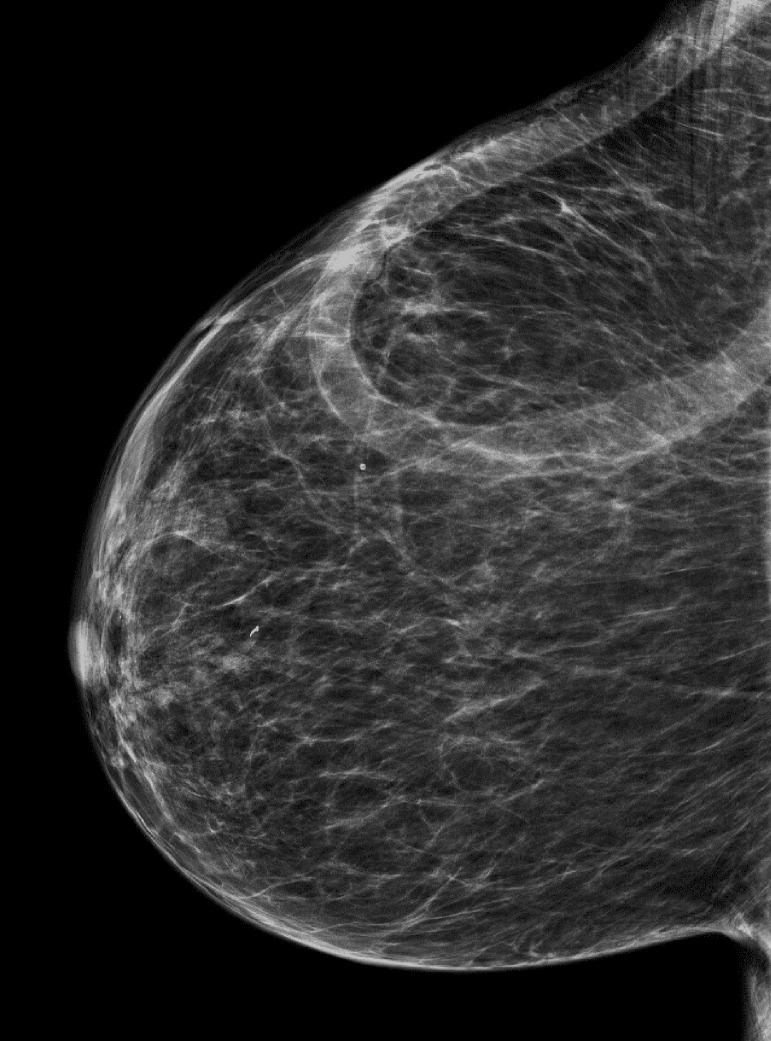

A 70-year-old African American woman with a known history of ESRD attributed to focal segmental glomerulosclerosis presented for dialysis access evaluation. Her past medical history was remarkable for hypertension, peripheral arterial disease, treated hepatitis C, stroke with residual right-sided weakness, gout, and diabetes. Her medications included metoprolol, amlodipine, cinacalcet, esomeprazole, and allopurinol. Physical exam was significant for multiple scars of old access surgeries on the upper extremities and a loop right chest AV graft with good bruit and thrill. In the background, the patient started dialysis in 2004 using a tunneled venous catheter; in late 2005, she underwent left upper arm arteriovenous (AV) fistula creation that lasted for 7 years till 2013 at which she received a deceased donor kidney transplant. With no further follow-up on its functionality, the AV fistula clotted. However, in 2016, the kidney transplant graft failed due to chronic rejection, and subsequently, the patient resumed hemodialysis via a tunneled venous catheter. Between 2016-2018, multiple attempts to create reliable dialysis access failed including upper extremity AV fistula and grafts. The etiology of access failure was attributed to non-maturation, immediate thrombosis, or severe steal syndrome that required access ligation. Notably, the patient declined peritoneal dialysis option. With her severe peripheral arterial disease and history of steal syndrome, the thigh AV graft option was excluded. Subsequently, she underwent right axillary artery to right axillary vein loop AV graft in September 2018 (post-operative access ultrasound is shown Fig. 1) that was used immediately for cannulation. Up till January 31, 2022, the chest AV graft has been functional without any intervention (Fig. 2). Interestingly, during a routine screening mammogram, the chest AV graft was seen very clearly (Fig. 3).

Fig. 3.

Mammogram showing clearly the chest loop AVG.